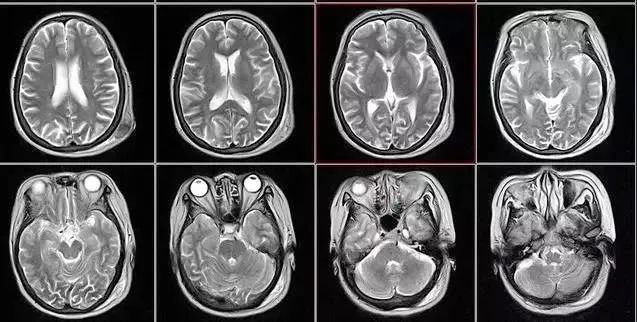

03、MR篇

這份影像檢查必備的“省心”秘籍,相信一定會幫助到您!

MR(核磁共振成像檢查)與CT檢查具有一定的相似之處,對于軟組織的成像分辨率更高,且沒有輻射。在臨床上的應用非常廣泛,用于檢查診斷神經(jīng)系統(tǒng)疾病、關節(jié)軟組織損傷,肝臟、盆腔病變優(yōu)勢明顯。